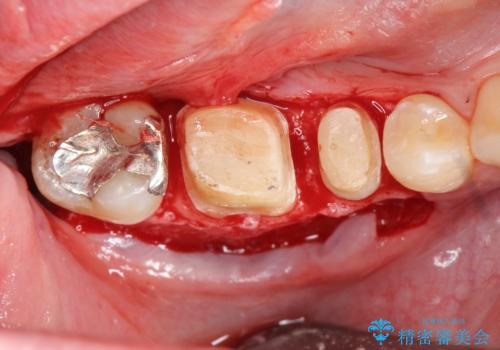

マイクロスコープを用いた根管治療を行ったのち、深い虫歯に起因する歯ぐきの腫れ・出血を改善すべく歯周外科を行いました。

歯周組織が落ち着くのを待ち、セラミッククラウンで機能・審美性を改善します。

歯内・歯周環境が整備されたことで長期的な予後の期待できるセラミック治療を行うことができました。